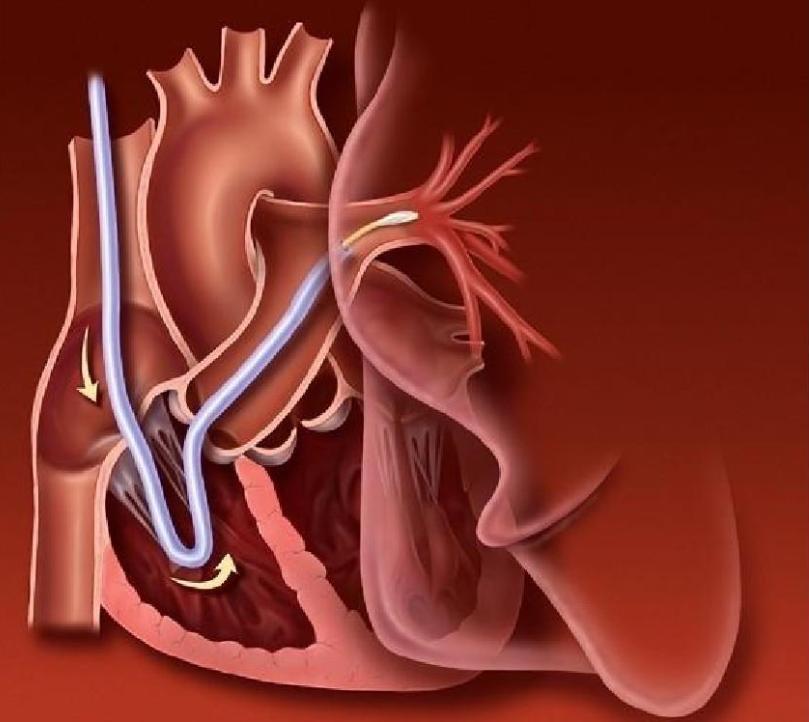

三、PCI有着很多的应用

目前最公认为是如果说在发病的几个小时内进行的紧急经皮腔内冠状动脉形成术(PTCA)及支架术,这种手段可以称为用来恢复心肌再灌注的手段,这种最安全、最有效的手段就叫做经皮冠状动脉介入治疗(percutaneouscoronaryintervention,PCI)。

它有着;(1)梗死相关血管再通率;(2)残余狭窄小的特点。

补救性PCI也可以用于溶栓失败没有达到再灌注的情况,当发生心肌梗死症状时,应该立即用恢复心肌再灌注的方式治疗,它不但能降低最近死亡发生率,还能预防以后的心力衰竭。